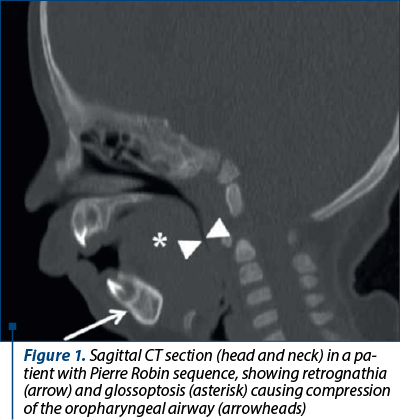

This technique is particularly useful in lip and/or palate cleft (CLP) for the visualization of bony and dental anatomy, and it is often used before plasty of dentofacial deformities; it is usually performed in patients with complicated or syndromic cleft palate as seen in the Pierre Robin sequence; multiplanar reconstructions of helical CT images, with the use of specific bone and soft tissue algorithms, can help visualize anatomical malformations, and three-dimensional reconstructions can facilitate surgical planning.

The size, shape and symmetry of the mandible can be well determined. Mandibular ramus length can be measured using reformatted oblique sagittal sections (mandibular ramus length of at least 17 mm is required to allow osteotomy and implant placement)(2). The identification of the inferior alveolar nerve foramen is important to avoid nerve damage during osteotomy in orthognathic surgery or of implant insertion(2). The existence and degree of airway obstruction can also be appreciated on the conventional CT examination (Figure 1).